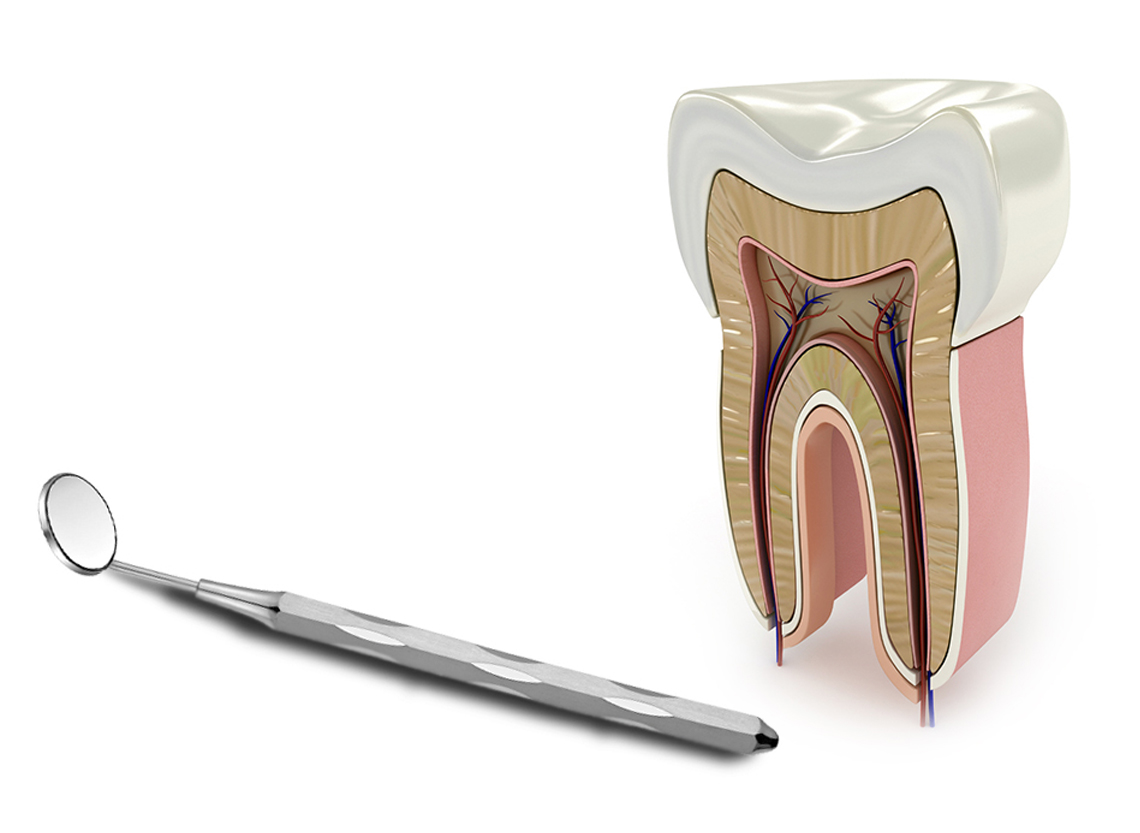

Laser ile Fotoakustik kanal temizliği

Kanal içine giren mikropların ortadan kaldırılması ve ardından sıkıca doldurulması esasına dayanan Kanal Tedavisinin gerçekleştirilmesinde foto-akustik ses dalgaları ile bakteri öldürme yeteneğine sahip Erbiyum laserleri kullanılır.